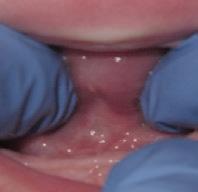

There Is Only One Smile That Matters. Yours!

You are in good hands! Dr. Makarita is the only accredited Fellow of the American Academy of Cosmetic Dentistry in Virginia.

BEFORE AFTER

At Tysons Aesthetic Dentistry Dr. Makarita has designed and equipped his practice with your smile in mind. Dedicated care and attention are just the beginning.

As a general dentist with a passion for aesthetic and cosmetic dentistry, whether a simple filling or a smile makeover, Dr. Makarita’s priority is to help you love your smile.

Since earning his doctorate from the Medical College of Virginia, Dr. Makarita has continually upgraded his skills and knowledge with continuing education so he can always bring you the most advanced options for all your dental needs.

Always welcoming new patients! Call 703-532-2020  8150 Leesburg Pike | Suite 503, Vienna VA 22182 www.ilovethatsmile.com

FREE SMILE EVALUATION In person or visit website for virtual smile consultation

Dr. H.R. Makarita

Accredited Fellow, American Academy of Cosmetic Dentistry

Master, Academy of General Dentistry

Master, International Congress of Oral Implantologists

Master, Las Vegas Institute for Advanced Dental Studies

to Love Your Smile? Dr. Makarita would love to meet you! About